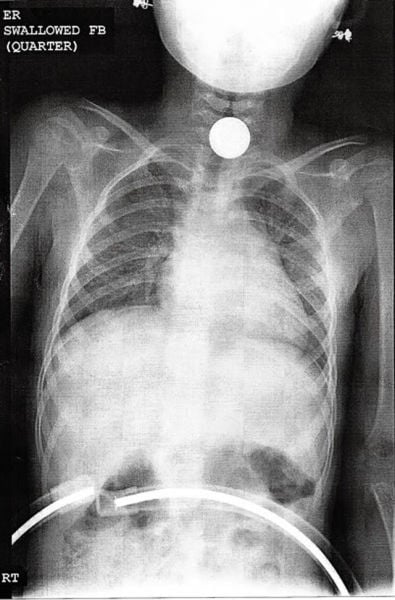

This X-ray that shows the quarter that was swallowed by a 6-year-old girl.